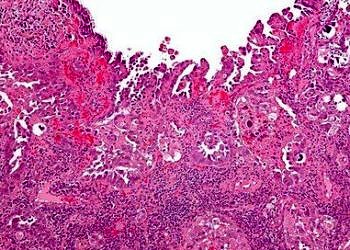

Dudak kanserleri, uzun süre güneş altında çalışan kimselerde ve sigara içenlerde daha sıktır; dudak kanseri, nazofarengeal karsinom'un nedenleri, belirtileri ve...